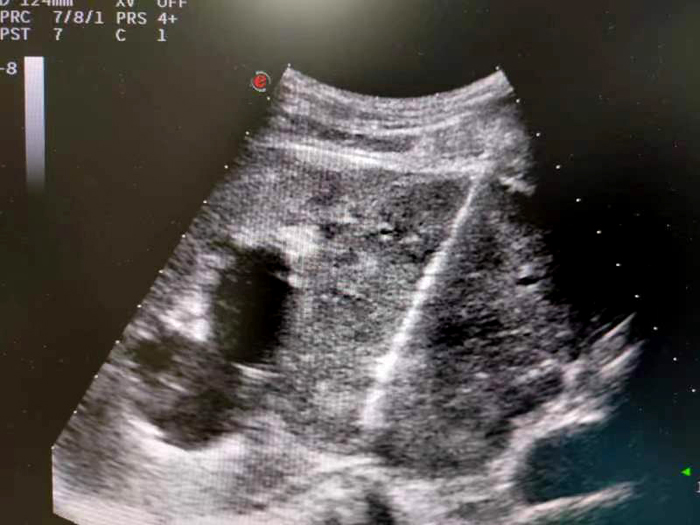

腎臟腫物穿刺活檢

適用于肝囊腫、腎囊腫、卵巢囊腫、巧克力囊腫、甲狀腺囊腫等囊性病變。方法是在超聲引導下,用一根穿刺針直接經皮膚刺入囊腫內,抽出囊液,注入硬化劑,拔除穿刺針,整個過程僅需20-30分鐘。經過3-6個月囊腫可以逐步吸收消失,5.0mm-8.0mm是治療最佳時期。該方法也是多囊肝、多囊腎較大囊腫理想的治療手段,無手術疤痕,無需縫合、換藥、拆線。

肝臟腫物微波消融術